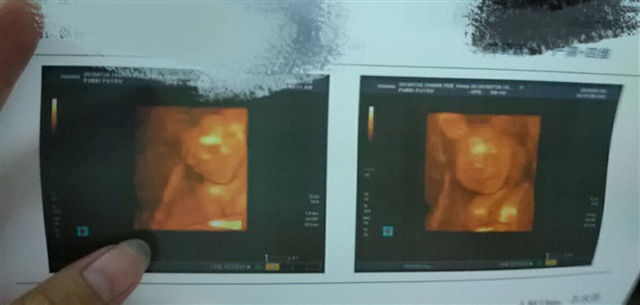

孕11周+3天

女孩几率大